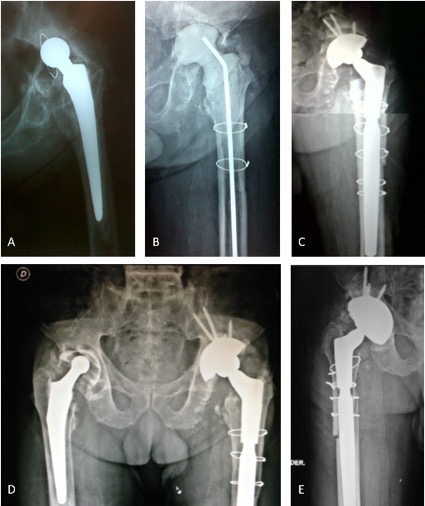

Uso de copas de tantalio trabecular para la reconstrucción acetabular compleja. Resultados de una serie de 42 casos y un seguimiento promedio de tres años.[Trabecular metal cup outcomes in complex acetabular reconstruction. Review of 42 cases with a 3-year follow-up].